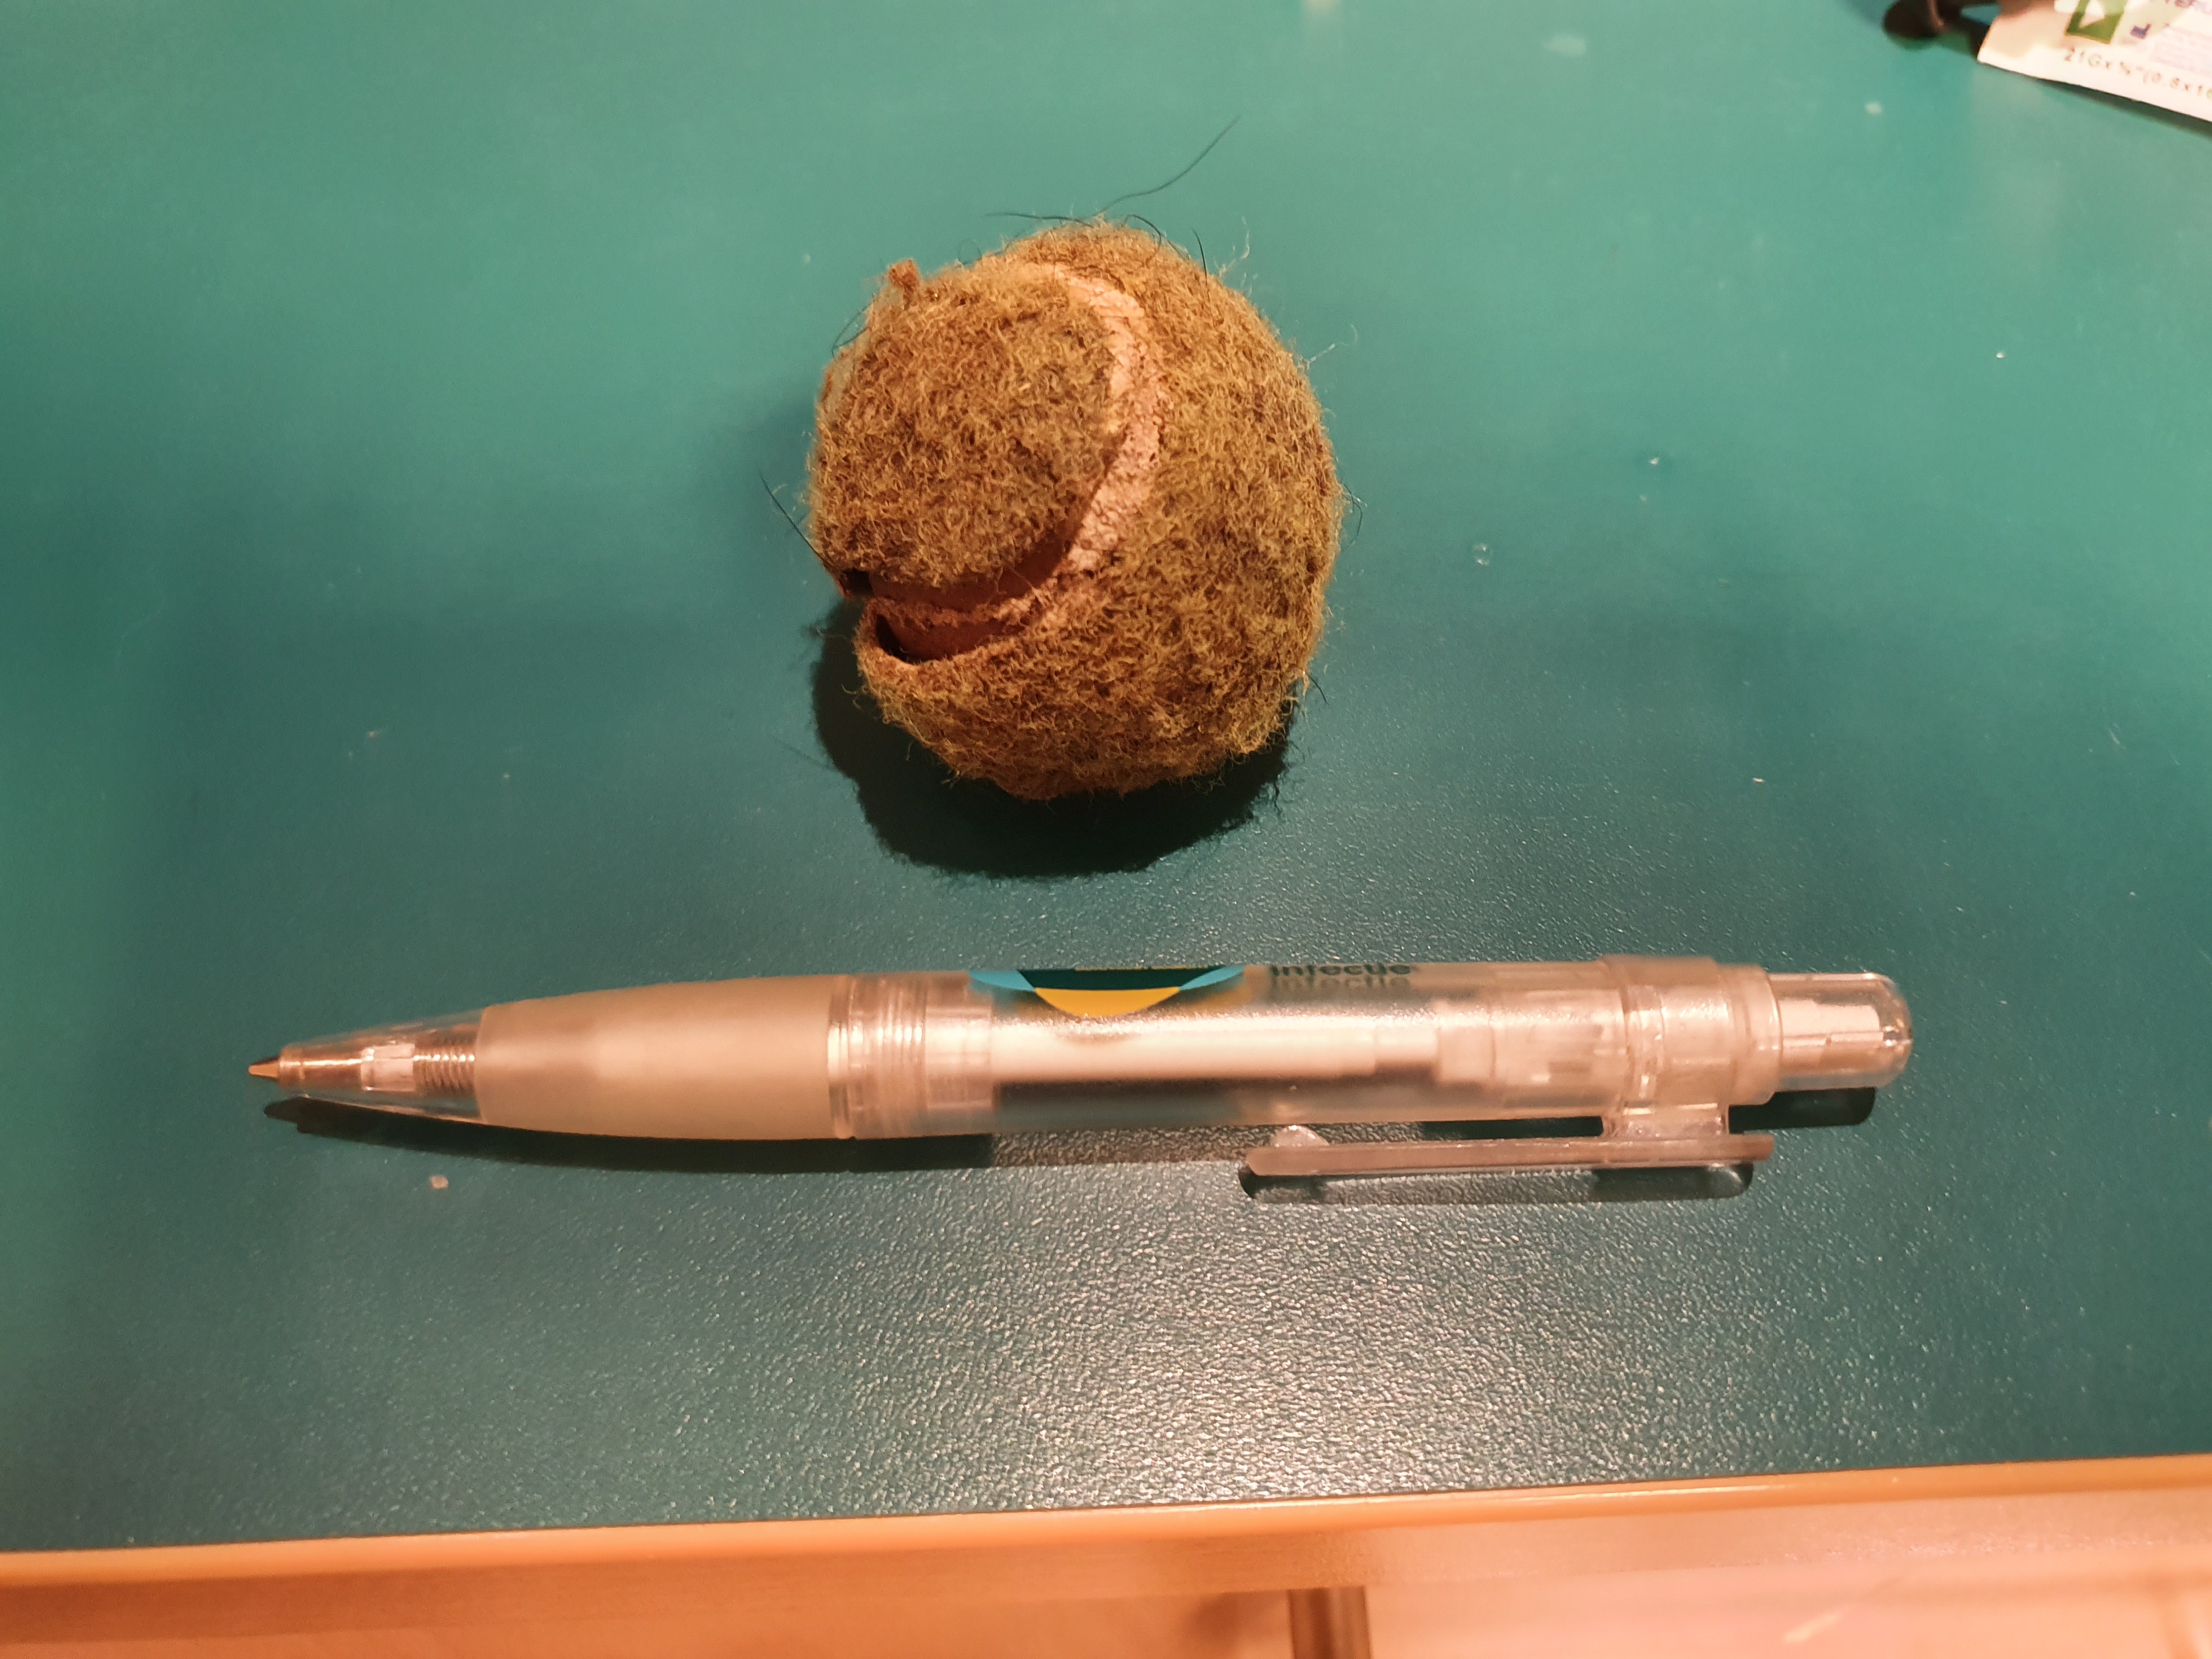

Het tennisballetje